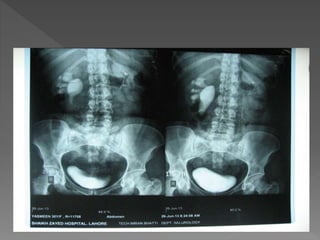

X ray films 1)Pre contrast 2) 5 mins 3) 25 mins 4) Post void

 The plainfilm demonstrates calcification within distended upper pole calyces